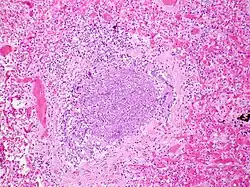

Physiopathologie

La période d'incubation est de deux à huit jours, puis le virus se multiplie dans la muqueuse nasale (une rhinopharyngite inaugure ainsi fréquemment une bronchiolite). Il gagne ensuite les voies respiratoires inférieures pour atteindre les bronchioles où il se multiplie, au sein des cellules épithéliales.

Le tableau clinique est dû à une obstruction des voies aériennes, d'une part causée par un bouchon muqueux obstruant la lumière, d'autre part due à une inflammation de la paroi bronchique. Le bouchon muqueux est créé par l'accumulation de cellules mortes et de sécrétions muqueuses. L'obstruction n'est que peu liée au spasme bronchique, les muscles lisses étant encore peu développés à cet âge.